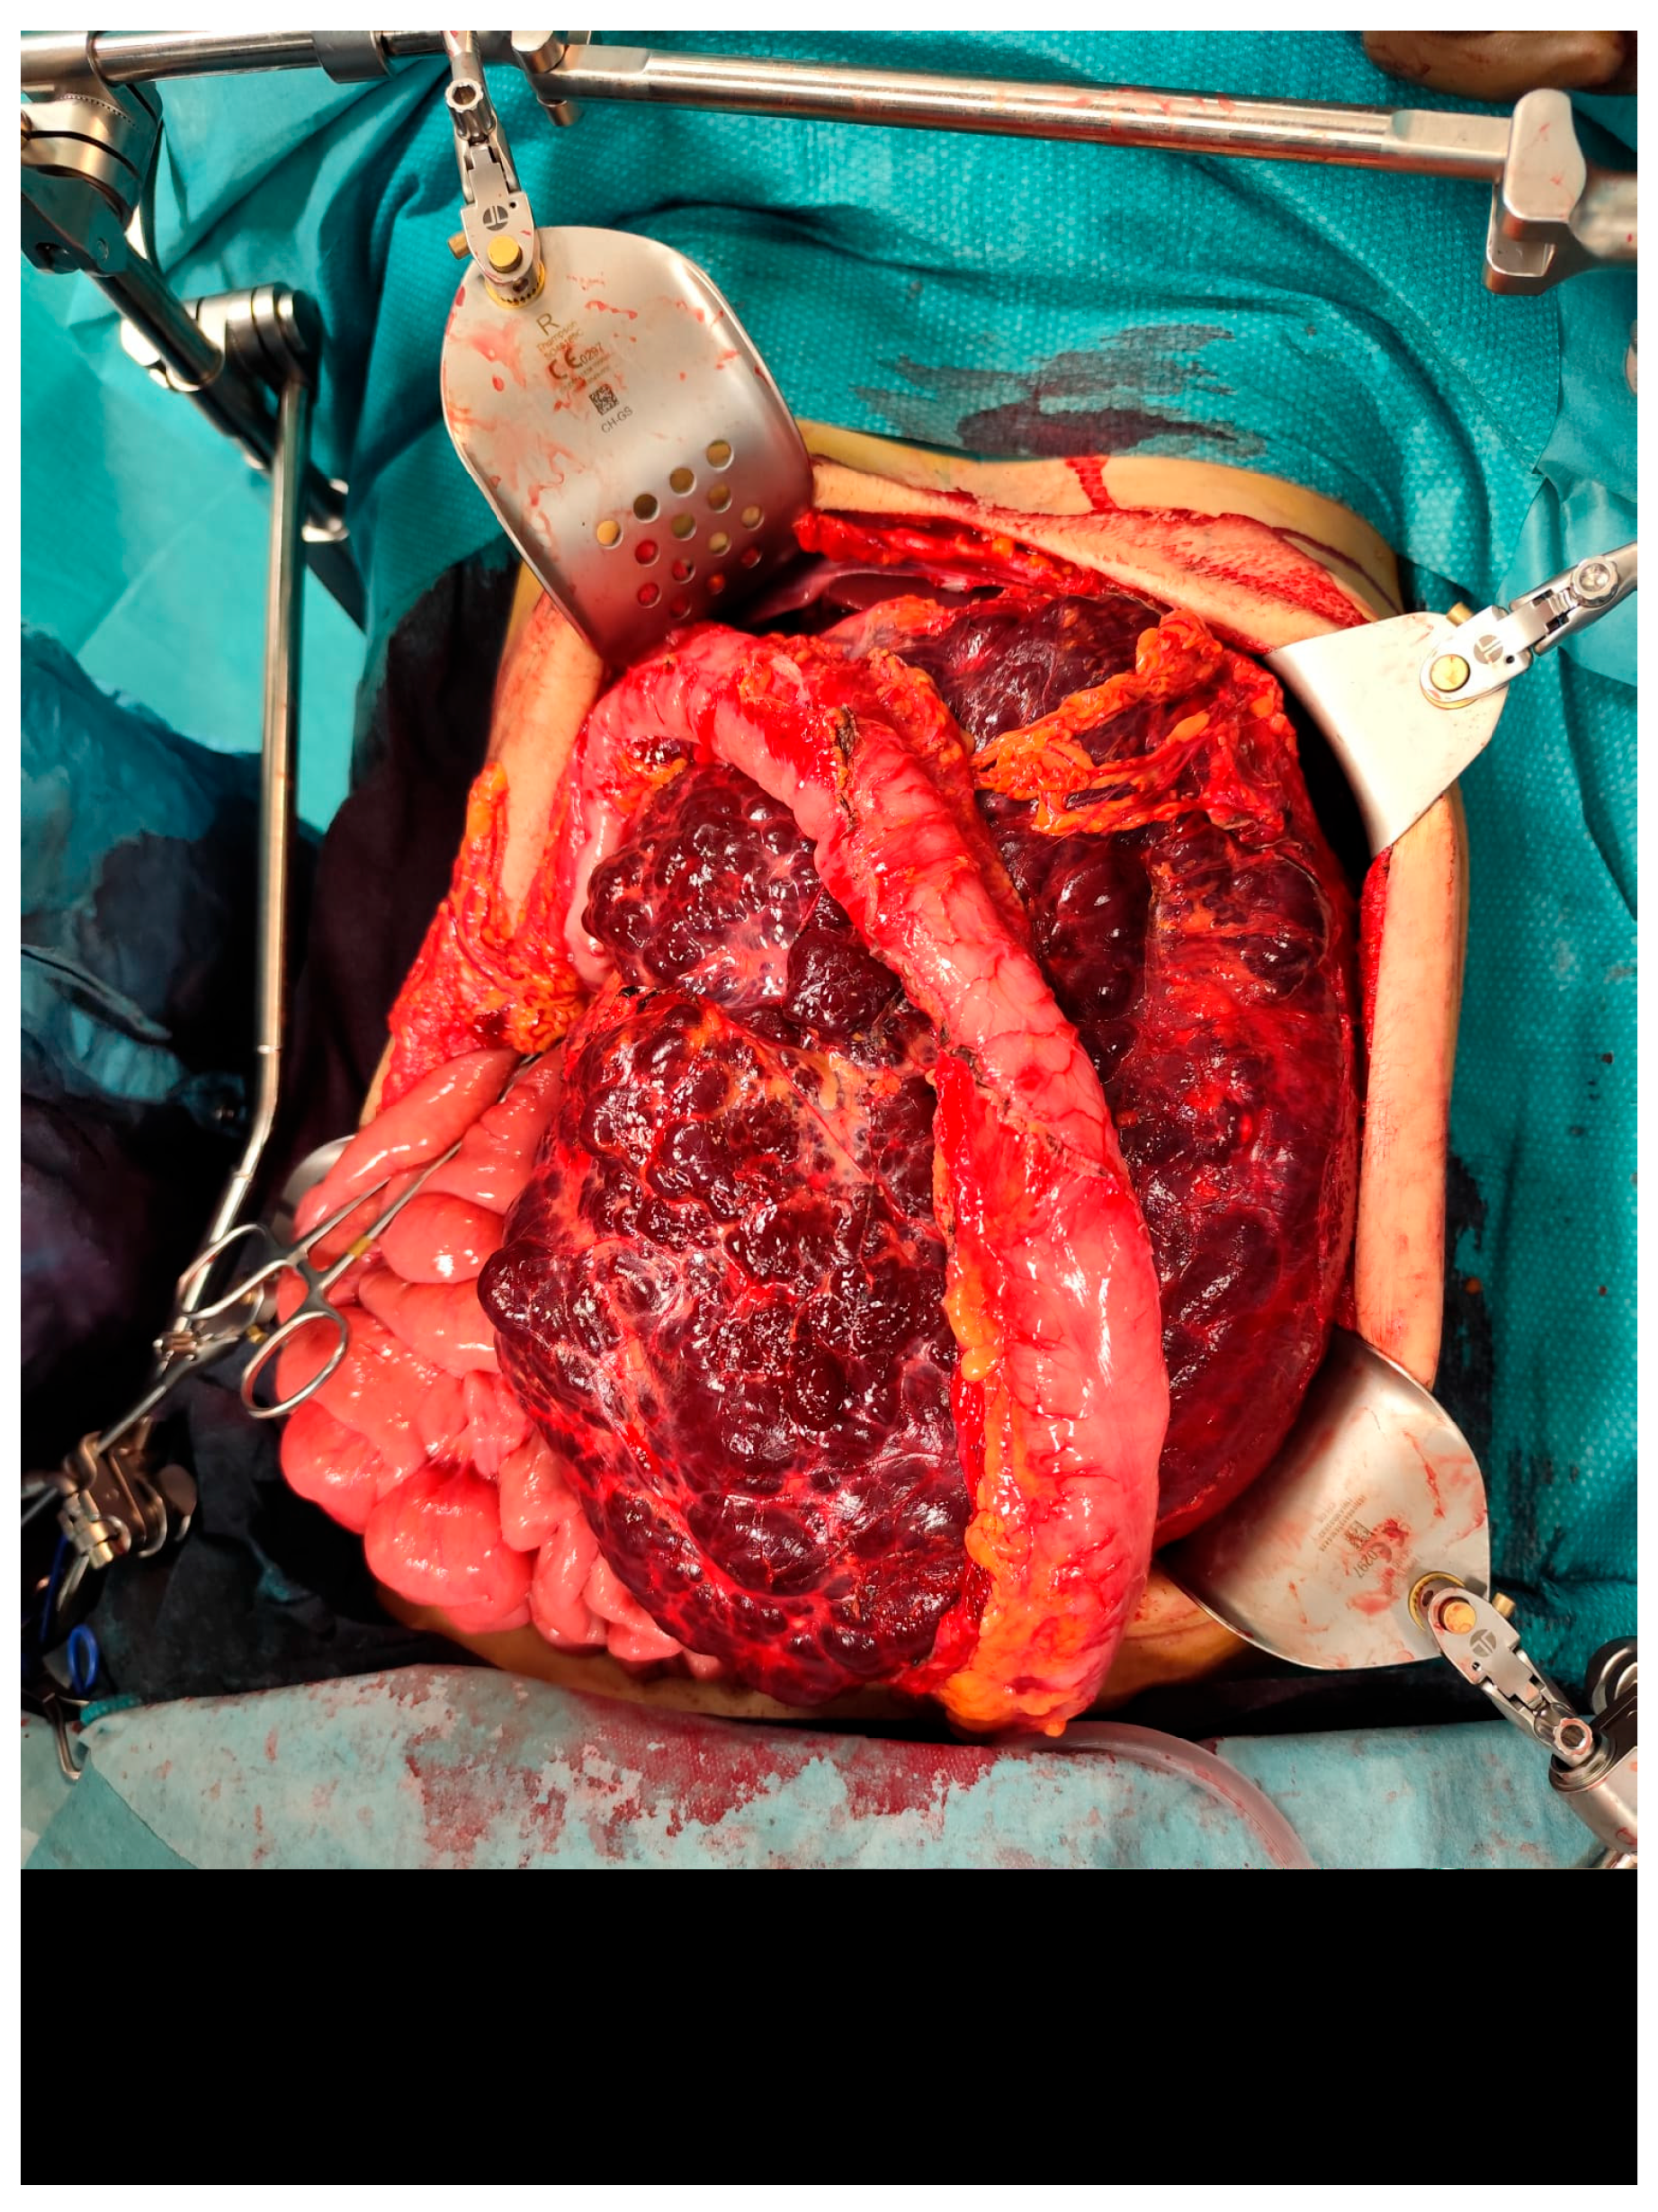

The case was discussed during the dedicated multi-disciplinary meeting, and due to the lesion’s considerable size and complex structure, as well as the inconclusive results of the biopsy, surgical resection was advised. The procedure included “en bloc” removal of the left kidney and adrenal gland, both of which were tightly adherent to the mass (Figure 4 and Figure 5).

Figure 4. Intraoperative picture showing the mass.